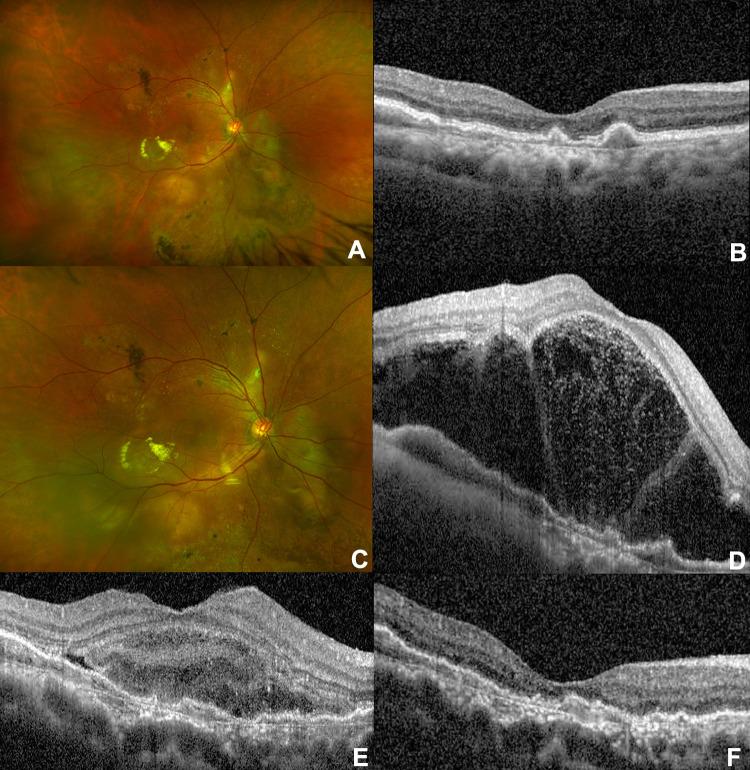

Photodynamic therapy (PDT) has a niche role in treating various choroidal pathologies. PDT-induced acute exudative maculopathy (PAEM) is an uncommon complication of PDT that results in exudative retinal detachment and mild to severe decrease in vision. Successful management strategies include observation, local or systemic corticosteroids, and intravitreal anti-vascular endothelial growth factor (anti-VEGF) injections. Most cases return to visual acuity near baseline. This review summarizes what is known about PAEM to date including etiology, prevalence, management strategies, and outcomes. We conclude that management of PAEM must take into consideration various patient-specific factors. Treatment with corticosteroids or anti-VEGF agents may expedite time to recovery, though lack of randomized controlled trials preclude firm conclusions regarding a standardized approach to managing this complication of PDT.

光动力疗法(PDT)在治疗各种脉络膜疾病中具有特定作用。PDT诱导的急性渗出性黄斑病变(PAEM)是PDT一种不常见的并发症,可导致渗出性视网膜脱离以及视力轻至重度下降。成功的管理策略包括观察、局部或全身使用皮质类固醇以及玻璃体内注射抗血管内皮生长因子(抗VEGF)。大多数病例的视力恢复至接近基线水平。本综述总结了迄今为止关于PAEM的已知信息,包括病因、患病率、管理策略和结局。我们得出结论,PAEM的管理必须考虑各种患者特异性因素。使用皮质类固醇或抗VEGF药物治疗可能会加快恢复时间,尽管缺乏随机对照试验,无法就管理PDT这种并发症的标准化方法得出确凿结论。